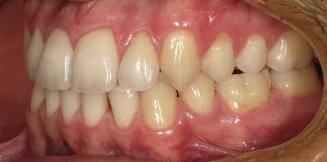

Dental Tribune Bulgarian Edition / октомври 2022 г.16 клиничен случай с алайнери Г орният латерален ре зец е вторият найчесто вродено липсващ зъб.1,2 Поради разполо жението му във видимата зона на усмивката лечение то на подобни случаи нала га мултидисциплинарен под ход, целящ отличен функцио нален и естетичен резултат. Налице са няколко лечебни мо далности, свързани с различ но разпределение на място то: първият вариант е орто донтско отваряне на място и възстановяване на липсва щия зъб с конструкция, под държана от съседните зъби3 или от имплант4, докато при втория подход разстоянията се затварят и премоларът заема мястото на канина.5 Изборът на лечебен подход трябва да бъде направен съв местно от зъболекар и паци ент въз основа на очакванията на последния и предвиди мостта на лечението. Множе ство фактори влияят върху това решение, като напри мер типа малоклузия, размера, формата и цвета на кучеш ките зъби6, оклузалните вза имоотношения (овърджет и овърбайт), лицевия профил, дължината на зъбната дъга и несъответствията в разме ра на зъбите.7 В настоящата публикация се разглежда случаят на жена в зряла възраст с вродена лип са на горен ляв латерален резец. Бяха приложени про зрачни алайнери за отваряне на място за единичен им плант и бяха постигна ти функционална оклузия и отлична естетика. ПРЕДСТАВЯНЕ НА СЛУЧАЯ Диагноза Пациентката бе на 32 годи ни, когато лечението започна, и първоначалното ѝ състоя ние бе следното (фиг. 1–3): липсващ горен ляв латерален резец; клас II, подклас I малоклузия; отклонение на горната сре динна линия вляво; Доклад на клиничен случай ЛЕЧЕНИЕ С АЛАЙНЕРИ НА ПАЦИЕНТ С АГЕНЕЗИЯ НА ЛАТЕРАЛЕН РЕЗЕЦ Д-р Iro Eleftheriadi и д-р Christodoulos Laspos, Гърция и Кипър Фиг. 1a–h Предоперативни лицеви и интраорални снимки. Фиг. 2a–e Дигитални модели преди началото на лечението. Фиг. 3 Панорамна снимка преди лечението. Фиг. 1a Фиг. 1d Фиг. 1f Фиг. 2a Фиг. 2d Фиг. 2b Фиг. 2e Фиг. 3 Фиг. 2c Фиг. 1b Фиг. 1e Фиг. 1g Фиг. 1h Фиг. 1c

Dental Tribune Bulgarian Edition / октомври 2022 г. 17клиничен случай с алайнери леко струпване в долната че люст; несъответствие по Болтън (мандибуларен излишък от 3.06 мм във фронталната зона и общо 1.47 мм); издължено лице с лицева аси метрия; конвексен профил с ретруди рана долна челюст и проми нентен нос. На мястото на зъб #46 бе на лице имплант, а зъби #16 и 26 са ендодонтски лекувани. Тези зъби бяха асимптоматич ни, затова бе взето решение да се прави релечение само при нужда. Мъдреците липсваха. Анализът на телерентгеногра фията (фиг. 4) показа ретрог натна мандибула (SNB: 74.2°) и нормална инклинация на резците както в

Цели на лечението и лечебен план Целите на лечението бяха следните: нивелиране и подреждане на зъбите и в двете зъбни дъги; отваряне на пространство за липсващия латерален резец; коригиране на отношенията при канините и моларите до клас I; и корекция на отклонението на срединната линия. Лечебният план включваше: корекция на отношенията при кучешките зъби и мола рите до клас I с дистализира не на максилата; отваряне на пространство в областта на #22 за поставя не на единичен имплант; корекция на срединната ли ния; и създаване на място за раз ширяване на зъб #12 и апрок симална редукция в долната челюст с цел подобряване на несъответствието по Болтън и осигуряване на подобра оклузия. Изпълнение на лечебния план Този случай бе изпълнен със системата за алайнери Invisalign (Align Technology). Одобреният първоначален лечебен план предвиждаше 49 алайне ра с дистализиране на задни те горни зъби до клас I (прибли зително с около 3.5 мм; фиг. 5). За бъдещия имплант в областта на липсващия латерал бе планирано пространство от 6.5 мм, докато във фронталния сегмент на долната челюст бе предвидена апроксимална редук ция. В дясната страна бутон за ластици клас II бе поставен на зъб #47 вместо на зъб #46, за да не се увреди короната на импланта. Понеже пациентката жи вееше в чужбина,

планта бе поставена временна коронка (фиг. 10 и 11), докато бъде изготвена окончателна та. Бе постигнат отличен кра ен резултат. Меките тъка ни около импланта напълно заздравяха, което доприне се за перфектната хармония между бяла и розова естетика (фиг. 12–15).

Dental Tribune Bulgarian Edition / октомври 2022 г.18 воначалния план. Тези пробле ми бяха адресирани чрез допъл нителна поръчка на алайнери с торк контрол и зададено екст рудиране на задните зъби с цел установяване на добри оклузал ни контакти в дисталните об ласти, като бяха предвидени и оптимизирани атачмънти с контрол над корените за корекция на ангулацията на макси ларните резци (фиг. 8). Резултати от лечението Панорамната рентгено графия след ортодонтското лечение показа благоприятна паралелна позиция на съседни те зъби, подходяща за поставя не на имплант в областта на #22, както и конвергенция на ко рените на зъби #44 и 45 (фиг. 9), но преценихме, че няма да от деляме допълнително лечебно време за коригирането ѝ поради факта, че пациентката бе мно го доволна от постигнатия до момента резултат. След при ключване на лечението бяха постигнати отлични взаимо отношения клас I при мола рите и канините, а срединни

съвпадаха. Върху им

(LFH: 56.5 mm) и размерите на меките тъка ни останаха непроменени. На клонът на горните резци бе за пазен (Ui–FH: 115.8°), а долните резци бяха леко наклонени ве стибуларно (Li–APog: 30°; фиг. 16). ДИСКУСИЯ Липсата на зародиш на по стоянен горен латерален резец е налице при 3.5–6.5% от евро пеидната раса, като при жени е по-честа, отколкото при мъ жете в съотношение 3:2.8–10 Възможни са няколко лечебни подхода, включително замя ната му с преоформен канин, отваряне на място чрез орто донтско лечение и протетич но възстановяване, както и ав тотрансплантация. Устано вено е, че изборът за затваря не на място или за отваряне то му все още подлежи на дис кусия сред ортодонти и проте зисти.11,12 Според литературните дан ни затварянето на простран ството и замяната на липсва щия латерал с канин се предпо чита в случаи на едностранна липса на зародиш, балансиран профил, кучешки зъби и премола ри със сходна форма и цвят, дву челюстна протрузия или клас II малоклузия.13–15 Отваряне на пространство по-често се изби ра при клас I, наличие на диасте ми и треми в горната зъбна дъга или голяма разлика в размерите на канини и премолари.16 Скорошно проучване е уста новило, че изборът на лечение при конгенитално липсващ ла терал е пряко свързан със след ните фактори17: възрастта на пациента при започване на лечението; индивидуалните особености при всеки конкретен случай; и сътрудничеството между специалистите в лекуващия екип. Макар да има проучвания, фа воритизиращи леченията със затваряне на място11,18, всеки случай трябва да бъде оценяван индивидуално. В презентирания в тази статия случай бе взето решение за отваряне на мяс то и протетично възстановя ване, понеже целта бе да се по стигнат клас I отношения при канините и моларите, както и по-широка усмивка. За да се из бегнат компромиси, след лече нието бе постигнат клас I при моларите и кучешките зъби, несъответствието по Болтън бе подобрено и срединната ли ния бе коригирана. Други изслед вания демонстрират отлични естетични и функционални ре зултати при лечение с отваря не на място и протетична ре хабилитация.19 И двете лечеб ни модалности са подходящи за третиране на вродена лип са на зародиш на латерал и да ват сходни функционални и па родонтални резултати20, като при едно проучване